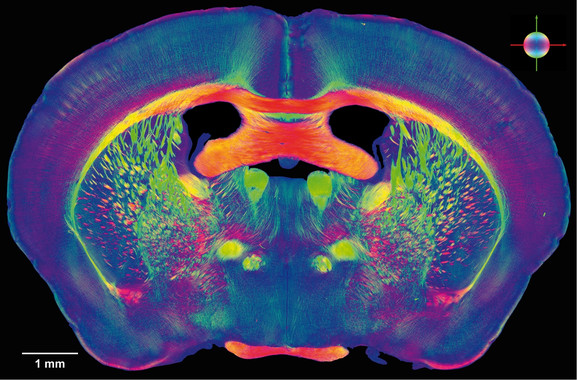

Para ello se registró la actividad magnética cerebral de cada uno de los participantes mediante magnetoencefalografía (MEG), una técnica que permite a los expertos estudiar la conectividad funcional entre distintas áreas cerebrales, o lo que es lo mismo, medir como se comunican entre sí las regiones del cerebro en cada uno de los participantes.

Al comparar al grupo de pacientes con deterioro cognitivo leve con el grupo control (personas mayores sin quejas de memoria) se encontraron alteraciones en la conectividad funcional de los pacientes cuyo cerebro ya había empezado a deteriorarse. Dichas alteraciones consistían en una importante desconexión entre regiones posteriores del cerebro, que disminuyen su comunicación, y que iban acompañadas de un aumento de conectividad entre ciertas regiones anteriores del cerebro. Sin embargo, el resultado más relevante del artículo es que las personas mayores con quejas subjetivas de memoria y sin deterioro cognitivo mostraban un patrón de alteraciones en su conectividad funcional muy similar al de los pacientes cuyo cerebro sí estaba deteriorado.